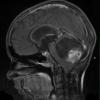

NEOPLASMS (GLIAL)

Astrocytoma, pilocytic - Microscopic (12)